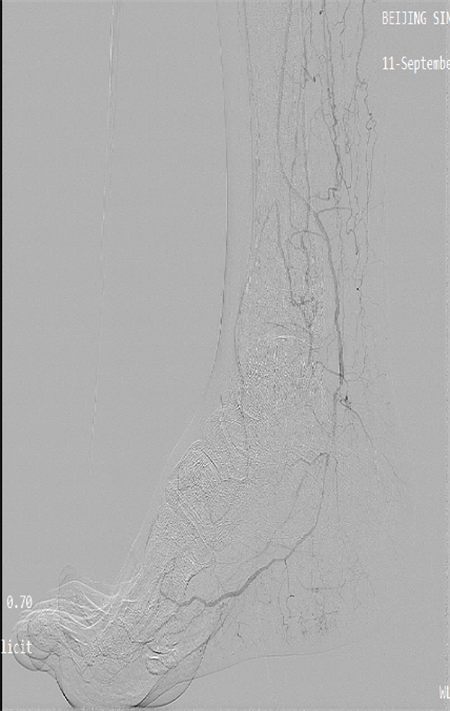

團(tuán)隊?wèi){借精準(zhǔn)的術(shù)前評估、規(guī)范的手術(shù)操作,成功為患者開通直達(dá)創(chuàng)面血管,改善創(chuàng)面供血。

術(shù)后患者恢復(fù)良好,足部溫度變暖,足跟部創(chuàng)面血運較前明顯改善,后期進(jìn)行中西醫(yī)結(jié)合創(chuàng)面換藥治療,未來可期。